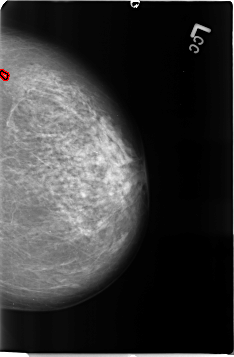

Digital Database for Screening Mammography

Volume: benign_04 Case: B-3361-1

B_3361_1.LEFT_CC

LEFT_CC LINES 4632 PIXELS_PER_LINE 3040 BITS_PER_PIXEL 12 RESOLUTION 50 OVERLAY

FILE: B_3361_1.LEFT_CC.OVERLAY

TOTAL_ABNORMALITIES 1

ABNORMALITY 1

LESION_TYPE CALCIFICATION TYPE PUNCTATE DISTRIBUTION CLUSTERED

ASSESSMENT 3

SUBTLETY 2

PATHOLOGY BENIGN

TOTAL_OUTLINES 1

BOUNDARY